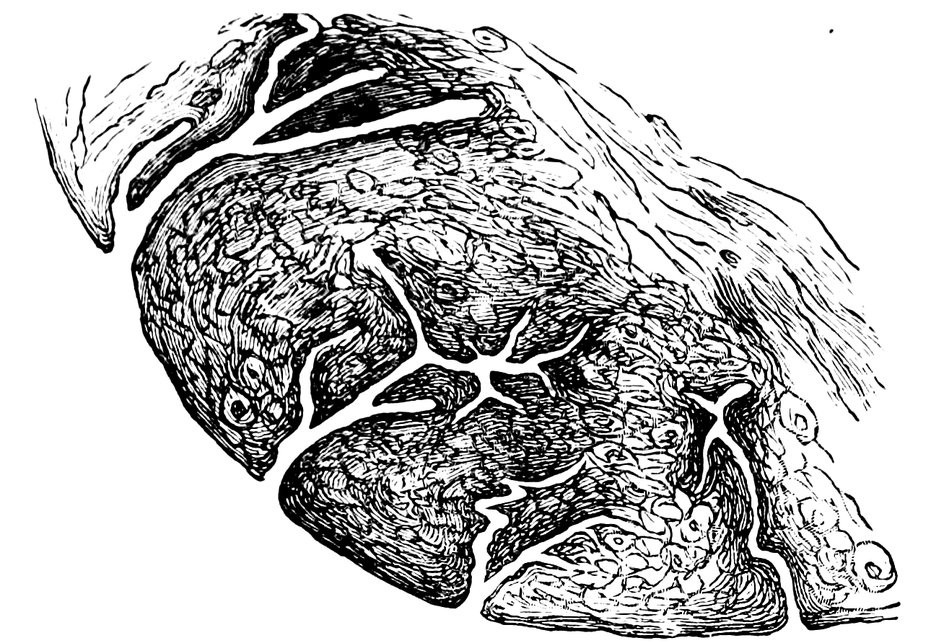

| 16. | Ripening follicles | 61 |

| 17. | Graafian follicles | 62 |